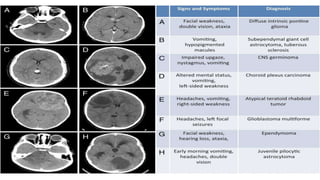

Tumour /CNS Malignancy

• Suggestive features

• Signs & symptoms of raised ICP

• Focal neurological deficit

• Seizures

• Extra-cranial primary malignancy

• Neuro-imaging: 1 st line investigation